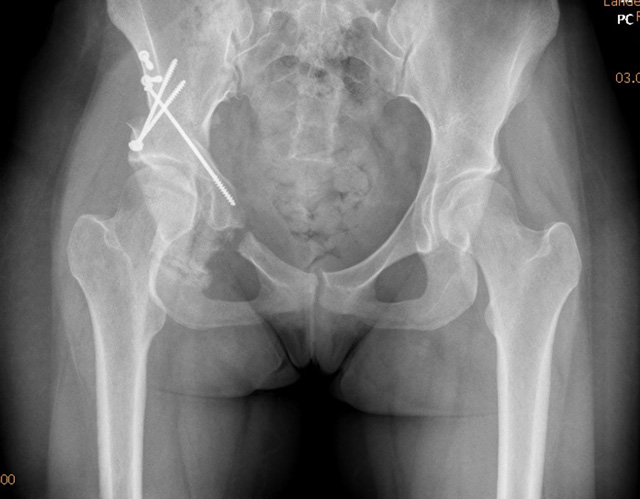

Bei der Operation wird der Beckenknochen in der Umgebung der Pfanne kontrolliert durchtrennt und die Pfanne dann neu orientiert und meist mit Schrauben wieder fixiert. Dadurch kann die Pfanne bezüglich Tiefe und Ausrichtung verändert werden.

Ganz-Osteotomie